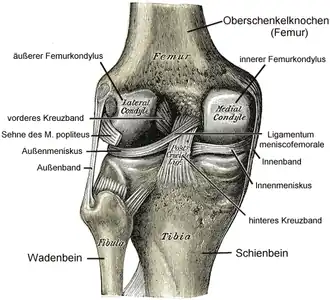

De knie of articulatio genus[1] is een gewricht in de vorm van een scharnierverbinding (articulus bicondylaris) in het menselijk been, dat het scheenbeen (tibia) verbindt met het dijbeen (femur, het bot van het bovenbeen). Deze verbinding wordt aan de voorkant beschermd door de knieschijf (patella). Het kniegewricht bestaat dus uit het femur, de tibia en de patella. Het is het grootste en meest complexe gewricht van het menselijk lichaam.

De voor-achterwaartse stabiliteit in het kniegewricht wordt vooral bereikt door kruislingse banden (de kruisbanden/ligamenta cruciformia) die boven- en onderbeen verbinden. De zijwaartse stabiliteit wordt gewaarborgd door de ligamenta collateralia. Een soepel scharnieren van het bovenbeen ten opzichte van het onderbeen wordt bereikt doordat de knie omvat is in een kapsel en door de aanwezigheid van kraakbeenschijven tussen de scharnierende botdelen (de menisci). Stabiliteit (passief) wordt bereikt door de kniebanden en kruisbanden en (actief) door de bovenbeenspieren.